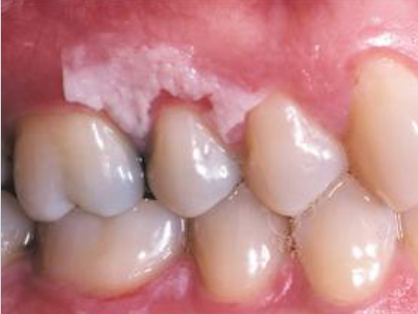

chemical burn

necrotic pseudomembrane that can be scraped off, due to chemical sensitivity

thermal burn

due to contact with hot food/beverage